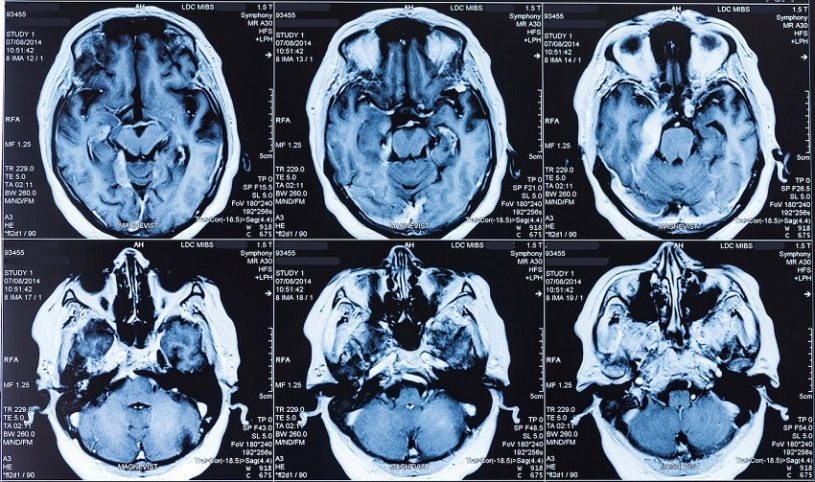

To find out, Vargas and Just put nine people in an MRI scanner and flashed an array of 28 abstract concepts at them, shown as words.